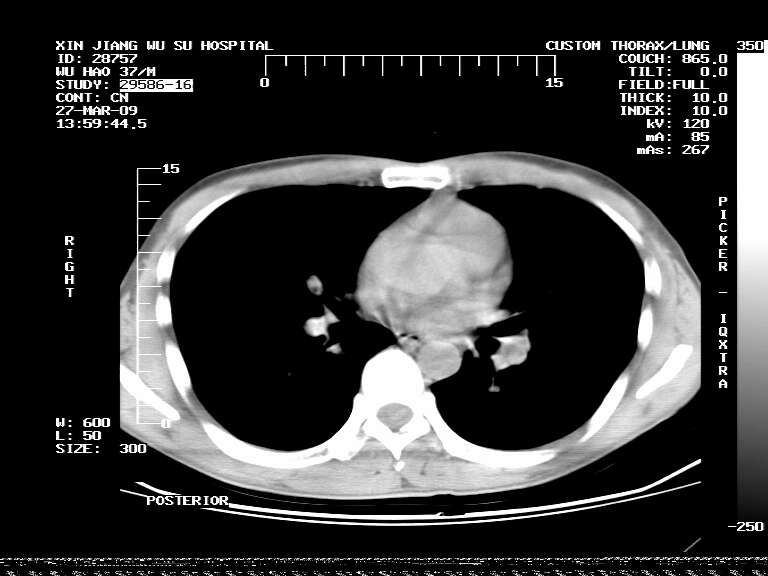

男,37岁,体检胸透发现阴影。

患者体检发现 无症状 左肺下叶占位,边缘模糊,可见血管聚束、分叶、胸膜牵拉,增强呈不均匀性强化。 首先考虑左肺下叶周围型肺癌,建议穿刺活检。

患者体检发现 无症状 左肺下叶占位,边缘模糊,可见血管聚束、分叶、胸膜牵拉,增强呈不均匀性强化。 首先考虑左肺下叶周围型肺癌,建议穿刺活检。支持!

左肺下叶见一结节病变,边缘欠清不光滑,与胸膜粘连且胸膜局限性增厚,注药后呈环形强化,动脉期壁呈明显点环状强化,静脉期壁强化减低,中心密度低无强化,灶周无明显的卫星灶和水肿区(晕征)---考虑周围性肺癌,不除外感染性病变,建议穿刺活检。

病灶强化太明显,病人较年轻。考虑炎性假瘤与周围型肺癌鉴别,以前者可能性,建议抗炎治疗后复查。

周围有卫星灶,胸膜反应不明显,病灶中心有坏死。建议先抗结核治疗后,短期复查